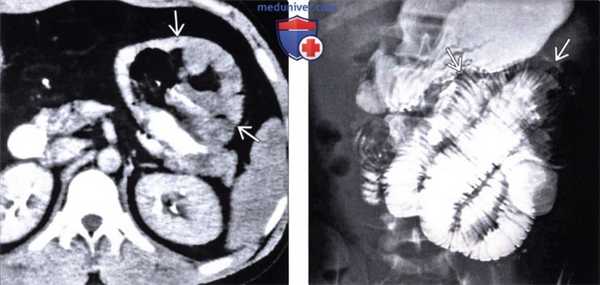

(Слева) На аксиальной КТ определяется правосторонняя парадуоденальная грыжа, которая стала причиной обструкции тонкой кишки. Обратите внимание на U-образную конфигурацию кишечной петли в грыжевом мешке.

(Справа) На корональной КТ с контрастным усилением определяется левосторонняя парадуоденальная грыжа, выглядящая «инкапсулированной» (типичное проявление). Обратите внимание на полнокровные брыжеечные сосуды, идущие прямо в грыжевой мешок.